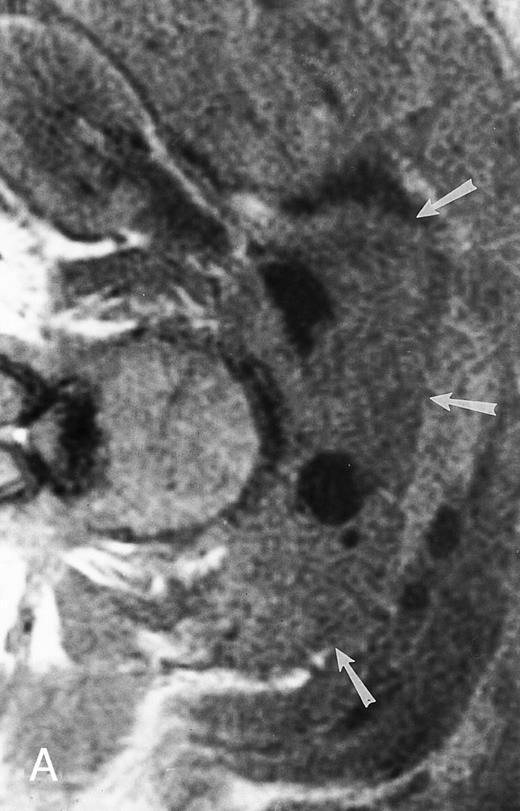

A 75-year-old woman with Waldenstrom macroglobulinemia: T1-weighted (600/20, TR/TE) axial (A) and sagittal T1-weighted (600/20, TR/TE) precontrast (B) and postcontrast (C) MR images of the lumbosacral spine. Note diffuse pattern of marrow infiltration and enlarged retroperitoneal lymph nodes (arrows). The abnormal marrow is isointense to the intervertebral discs on the precontrast image and enhances markedly becoming hyperintense to the discs on the postcontrast image.